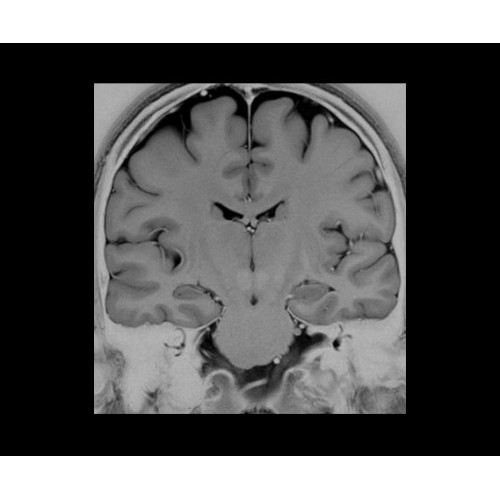

SIGNA PET/MR 3.0T — это гибридная система, в которой совмещаются две принципиально разные технологии — магнитно-резонансную томографию (МРТ) и позитронно-эмиссионную томографию (ПЭТ). Система отличающийся высокой чувствительностью и эффективностью и предназначена для диагностики в области онкологии, неврологии, кардио-васкулярных исследований, исследований воспалительных процессов.

Компания GE Healthcare представляет революционную, полностью интегрированную систему SIGNA PET/MR1, в которой сочетаются времяпролетная технология (TOF) и возможности напряженности магнитного поля 3.0 Тл. Мы поможем вам поднять исследования на более высокий уровень. SIGNA PET/MR позволяет достичь впечатляющей точности и скорости исследований, а благодаря новейшей технологии реконструкции Q.Clear2 качество изображений улучшается в два раза. Кроме того, в систему включен полный набор клинических приложений и гибких катушек для проведения любых видов исследования, открывая для вас возможности визуализации, о которых вы даже не догадывались.

В системе SIGNA PET/MR есть все инструменты, необходимые для выявления маркеров разных заболеваний и для создания новых протоколов. ПЭТ/МРТ можно использовать совместно с мультиядерной спектроскопией в лаборатории in vivo для изучения быстрых биохимических процессов. Кроме того, PET ToolBox и набор инструментов Orchestra предоставляют персональный доступ к функциям реконструкции изображений для ПЭТ и МРТ, ускоряя и упрощая работу с необработанными данными.

• Специальный пакет приложений для измерения и сравнения объемных изображений ЦНС с нормами поможет вам в диагностике нейродегенеративных заболеваний, а дополнительные инструменты визуализации — в постановке точного диагноза с помощью бета-амилоидов и радиоизотопных маркеров ФДГ.

• In vivo лаборатория — получайте полные данные биохимических процессов in vivo с мультиядерной спектроскопией на SIGNA PET/MR.